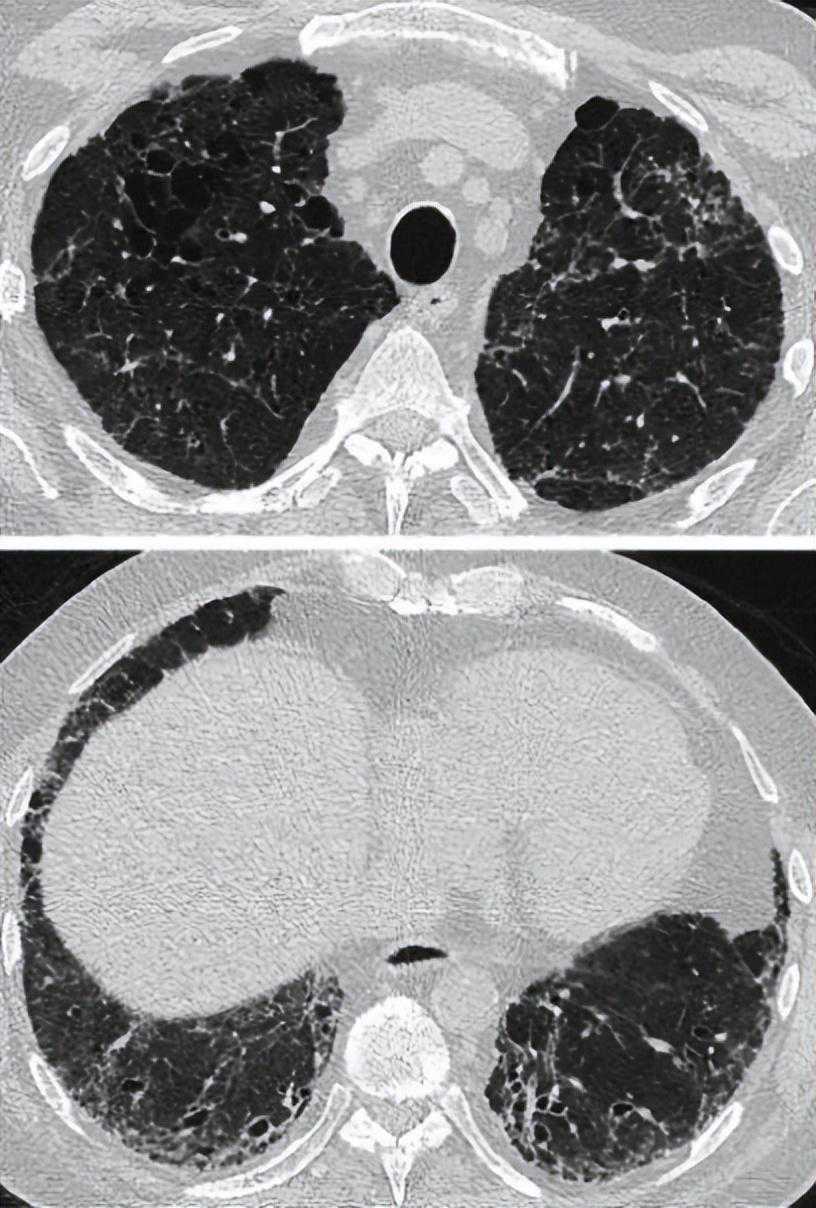

肺气肿是指CT上不以可见壁为界的低密度区[139]。可分为小叶中央型、间隔旁型或全腺泡型[140]。间质纤维化被认为是实质衰减增加的区域,表现为网状影和/或磨玻璃样阴影,以及不同程度地蜂窝状和/或牵拉性支气管扩张(表5)。HRCT上CPFE的肺气肿模式初步被分为不同的组[129,141-143](图1-8);然而,为了更好地定义CPFE的影像学亚型,还需要更多的工作。没有研究正式比较CPFE和COPD的肺气肿模式[140]。

图1:HRCT显示合并肺纤维化和肺气肿的典型疾病分布(单独的肺气肿和纤维化模式)。间隔旁和小叶中央肺气肿局限于上肺,以牵拉性支气管扩张为特征的纤维化局限于下肺。

图2:HRCT显示合并肺纤维化和肺气肿的典型疾病分布(进行性转变模式)。一例72岁特发性肺纤维化患者,主要表现为肺上叶小叶中央型肺气肿,并向肺中部扩散。下肺未见肺气肿。这些表现符合肺纤维化和肺气肿合并的进行性过渡模式。